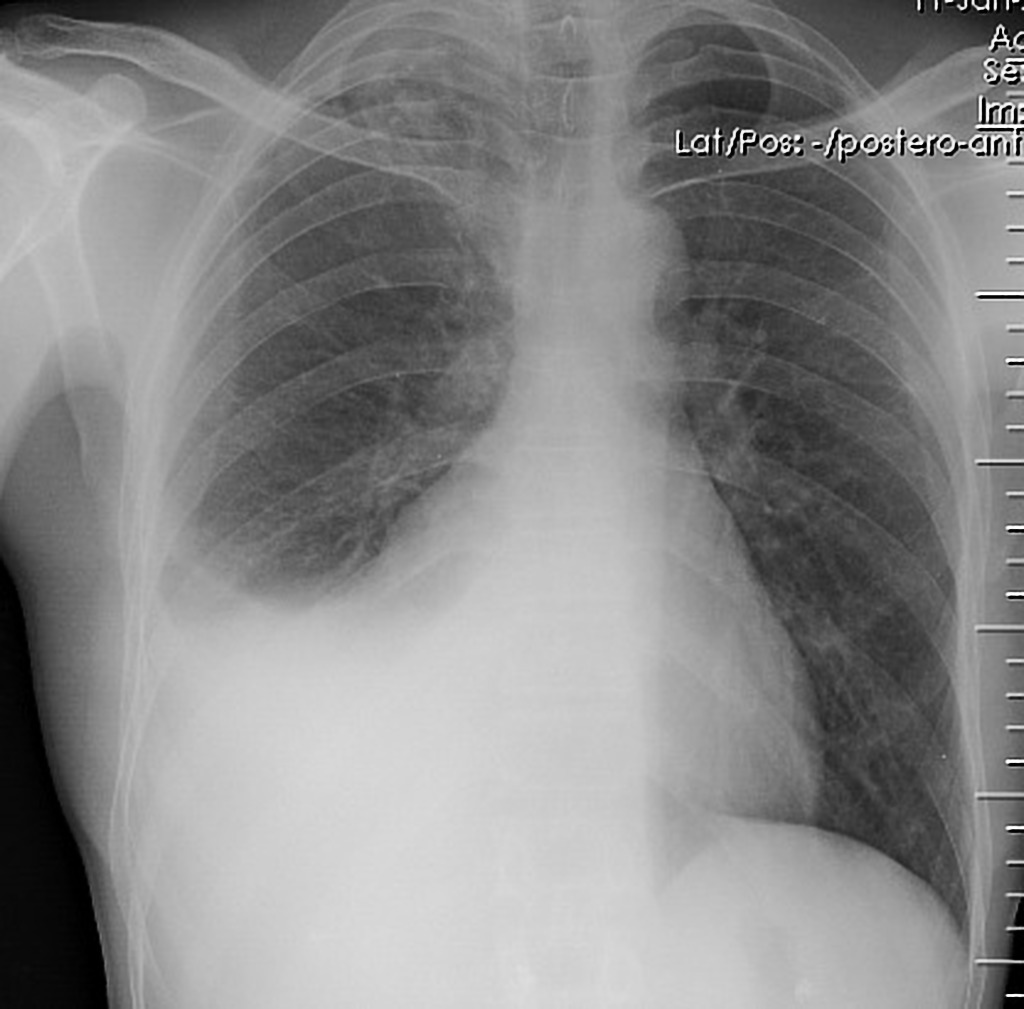

x ray of PE